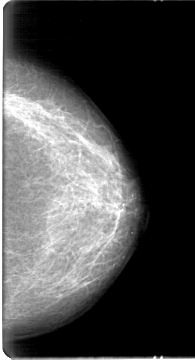

D_4046_1.LEFT_MLO

LEFT_MLO LINES 5386 PIXELS_PER_LINE 3151 BITS_PER_PIXEL 12 RESOLUTION 43.5 NON_OVERLAY